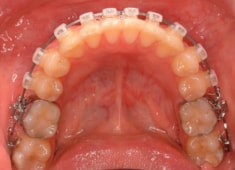

治療開始時